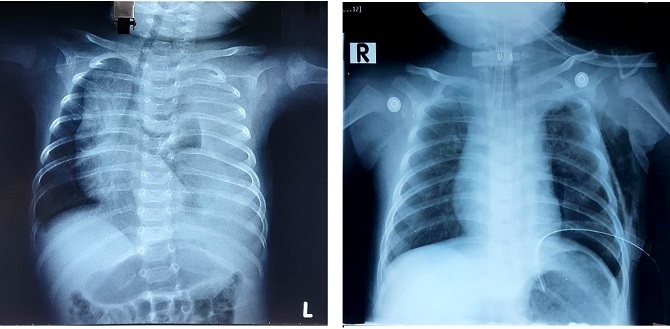

Ảnh X-quang bên phải cho thấy phổi nở đều bình thường sau khi được thắt ống ngực so với lúc đầu (ảnh trái). Ảnh:BSCC